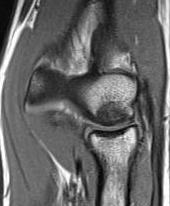

MRI

Fluid interface denotes detachment / instability

MRI Classification

Stable

- cartilage intact

- no fluid behind lesion

Unstable

- cartilage breach

- fluid behind lesion